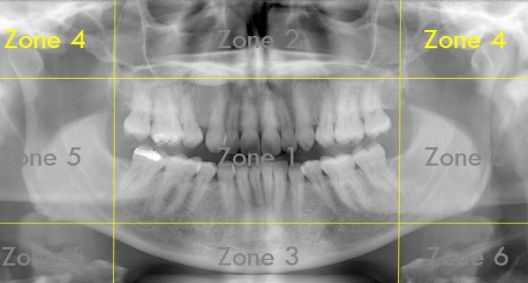

Identify The Zones.

Zone 1: Dentition

Zone 2: Nasal Cavity and Maxillary Sinuses

Zone 3: The Mandible

Zone 4: Temporomandibular Joints (TMJs)

Zone 5: Spine and Ramus

Zone 6: Hyoid Bone